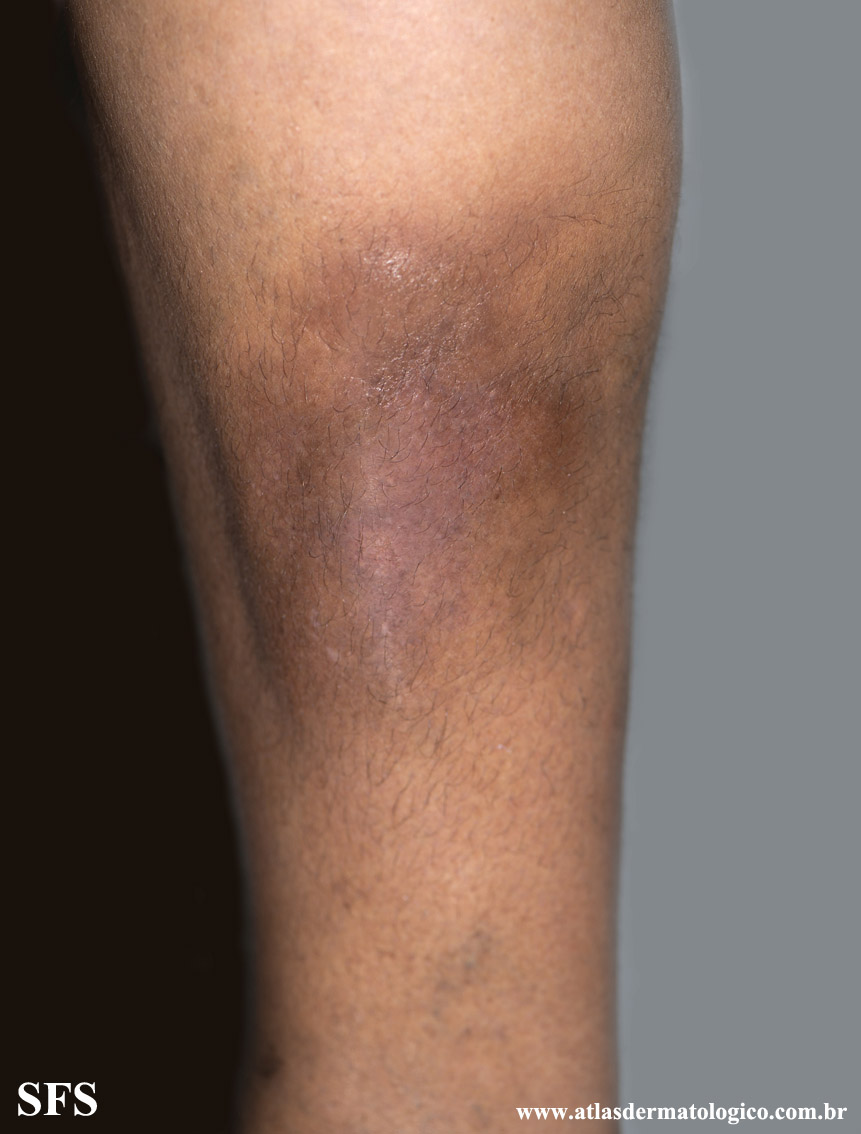

lipodermatosclerosis